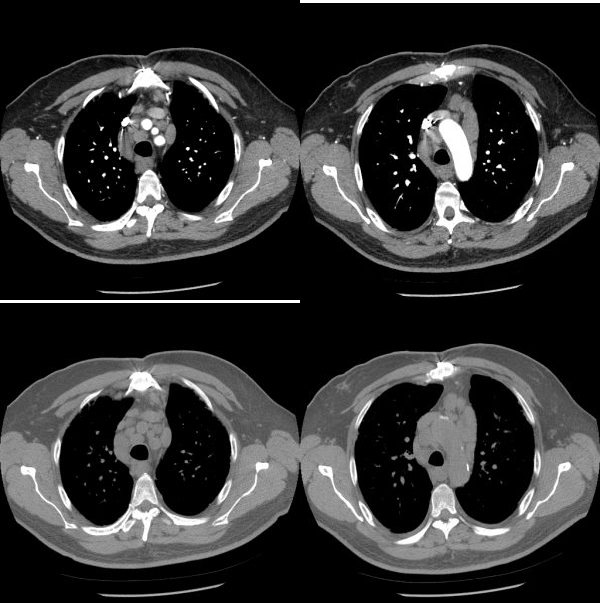

Age: 66

Sex: Male

Indication: Chest pain

Sample ReportWidening of the right paratracheal stripe, which raises concern for lymphadenopathy. Recommend chest CT for further evaluation.

Mild interstitial pulmonary edema with small bilateral pleural effusions.